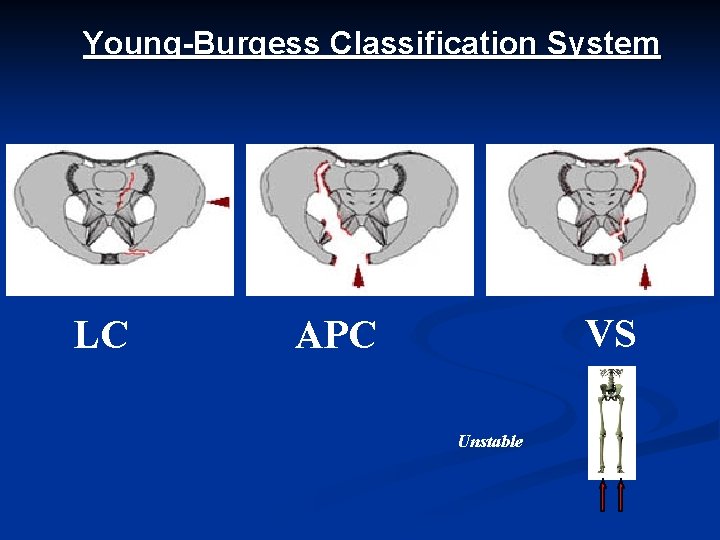

Young-Burgess Classification System LC VS APC Unstable